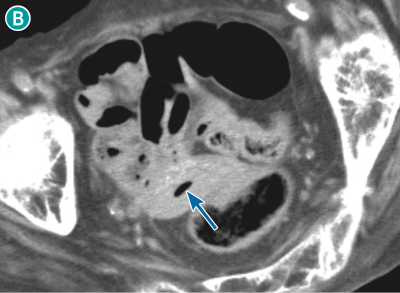

図 nonsurgical pneumoperitoneumの一例(単純CT,脂肪条件)

90歳代女性で発熱を主訴に来院.下腹部レベル(🅐)では,腸間膜を主体に複数の小さな腹腔内free air が認められる( ).骨盤部レベル(🅑,🅒)では,子宮( ![]() )および膣(

)および膣( ![]() )の腔内にもairが認められる.本例は消化管穿孔はなく,女性生殖器の感染により生じたairが腹腔内に移動したものと考えられた.

)の腔内にもairが認められる.本例は消化管穿孔はなく,女性生殖器の感染により生じたairが腹腔内に移動したものと考えられた.